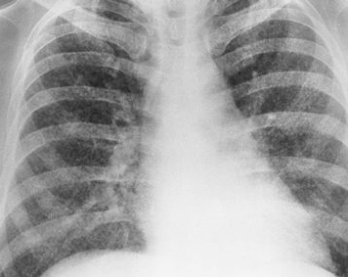

RA: covid-19

multiple bilateral patchy consolidations or opacities